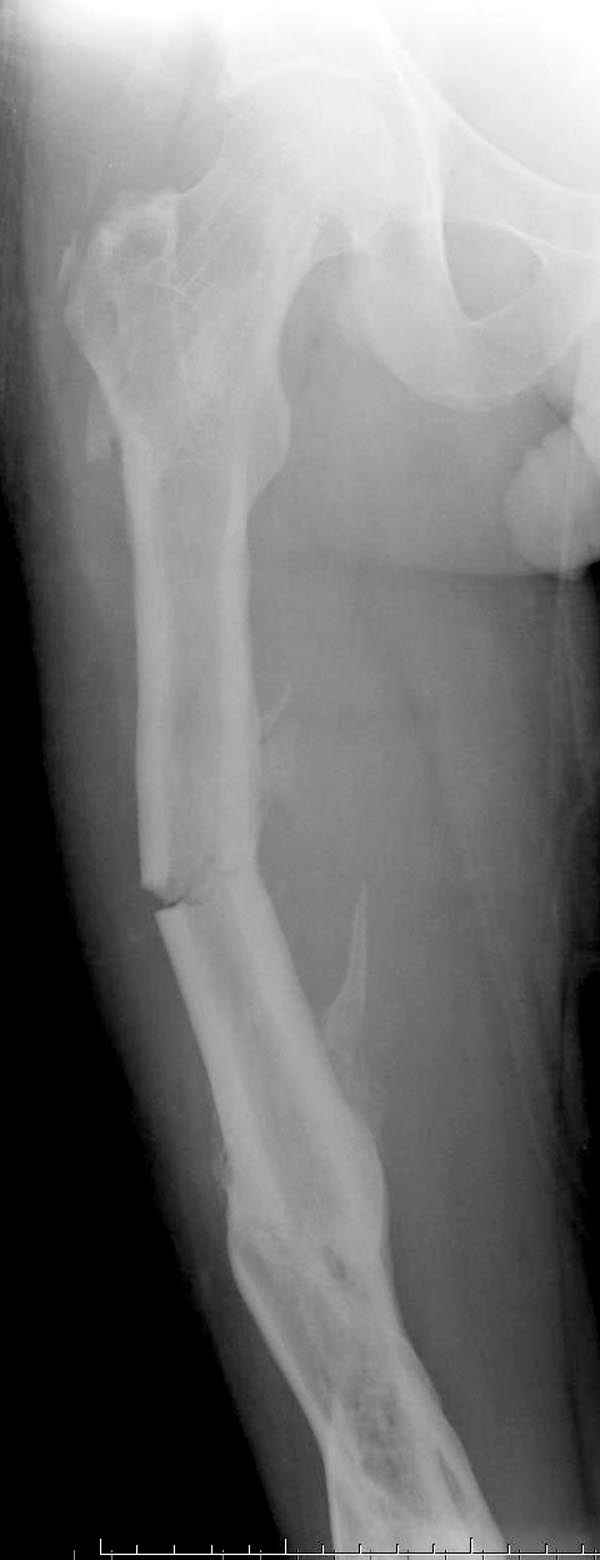

Мы не дождались “Happy End”, у больного IQ в пределах 70%, через 6 месяцев вернулся после небольшой травмы, споткнувшись получил перелом

того же бедра (рис №7).

На следующий день произвели интрамедуллярный остеосинтез: этапы во время операции (рис №8, №9)

При обзоре причин перелома, на снимке №2 обнаружили, что один из стержней аппарата наружной фиксации проходил только через передний кортекальный слой, что создало стрессовую зону на бедре и в результате перелом из-за незначительной травмы.